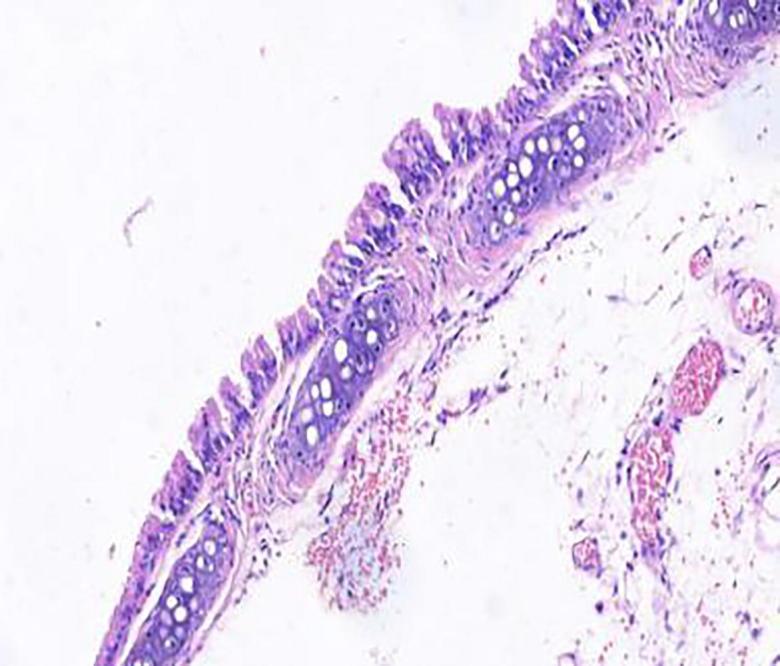

Compared with model group, the Schisandrae Fructus syrup groups can significantly increase the tidal volume of mice and decrease the respiratory frequency and the degree of bronchial stenosis ( < 0.01); The Schisandrae Fructus syrup groups can decrease the levels of NO and IL-6 in serum and improve the pathological changes of lung and bronchus in different degrees.

与模型组相比,五味子糖浆组可显著增加小鼠潮气量,降低呼吸频率及支气管狭窄程度(P<0.01);五味子糖浆组可降低血清中NO和IL-6水平,不同程度改善肺及支气管的病理变化。